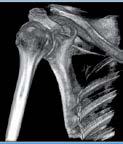

Nell’ambito della radiologia 3D ortopedica, il centro diagnostico utilizza il nuovissimo macchinario NewTom 5G XL, in grado di individuare con la massima precisione la presenza di fratture o lussazioni delle articolazioni, controllare la corretta guarigione di una frattura, valutare una lesione o una ferita causata da infezione, artrite o crescita anormale dell’osso.

Il tutto mediante una semplice e veloce scansione, grazie alla quale si otterranno diverse immagini in 3D ad altissima risoluzione e, per ottenere immagini ancora più nitide mediante un bassissimo dosaggio di radiazioni, gli esperti si avvalgono dell’innovazione racchiusa nella tecnologia Cone Beam.

Se con la radiologia tradizionale era necessario eseguire scansioni multiple, la novità introdotta dal macchinario NewTom 5G XL risiede nella capacità di fornire immagini ad alta risoluzione in un’unica scansione, mostrando nitidamente i dettagli delle articolazioni degli arti superiori e inferiori. Inoltre, a differenza della tecnologia 2D, la radiologia 3D ortopedica permette di individuare immediatamente alcune patologie come quella del metatarso, la quale richiede un allineamento visivo dedicato o una diagnosi delle micro fratture ossee.